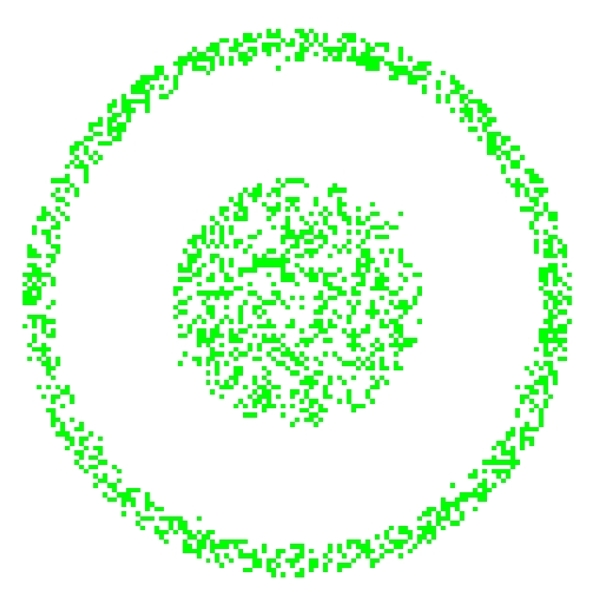

The first simulated data set consisted in a sequence comprising 100 3D-images. Each image ( voxels) was composed of four partially overlapping and concentric tubes. Each tube contained a single signal in its non overlapping part and a sum of two signals in its parts that intersect with another tube. For single signals, we used, from the central tube to the peripheral one respectively, a sinusoid (, ), a square wave (, ), a sinusoid (, ) and a square wave (, ). The background, which overlaps the tube at the periphery, contained, in its non overlapping part, a Gaussian noise (sd=0.2) (see Figure 3). Thus, four pure signals and four mixed signals were considered. To be realistic, we also added everywhere a Gaussian noise (sd=0.1).

We applied temporal and spatial ICA to these simulated data. Figure 5 shows the time course of the different extracted components and their spatial localization. It is interesting to note that temporal ICA extracted automatically four components with relevant time course and localization that appears correct using our R function \codef.plot.volume.gui(). The computed frequencies of the time course of these components were respectively, when ordered from center to periphery, nearly equal to 1/11 Hz, 1/10 Hz, 1/16 Hz and 1/4 Hz with phase difference (modulo ) with the corresponding original source signal. We used R functions \codeMod(fft(signal)) and \codeArg(fft(signal)) to compute these quantities. Spatial ICA extracted automatically, in the non overlapping parts, four spatial components with form and localization approximatively comparable to the initial sources. The first one (central tube) was not extracted. Note that each extracted component was associated with one of the original sources. This association was made based on the higher absolute value of the correlation between the time course of the component and each one of the four original signals. Thresholded localization of a specific component was then computed by keeping its voxels with values higher (resp. lower) than their empirical quantile of order 0.9 (resp. 0.1) if the correlation of its time course with the associated original signal was positive (resp. negative). The frequencies of the time course of the extacted components 1 to 4 were found to be, respectively, nearly equal to 1/4 Hz, 1/10 Hz, 1/16 Hz and 1/16 Hz, with phase difference (modulo ) with the corresponding original source signal. The localizations were less accurate than the ones obtained with temporal ICA. This is not surprinsing. Indeed, a nonparametric test for the mutual independence between our source time signals was performed using the R package \pkgIndependenceTests (for more information see Bilodeau and Lafaye de Micheaux (2010), Beran et al. (2007) or Bilodeau and Lafaye de Micheaux (2005)).

It was not possible to detect any form of dependence among these four source signals (see Figure 4). On the other hand, the spatial sources were not (spatially) independent because of their overlapping parts, and indeed only portions with pure signal were correctly extracted using sICA.